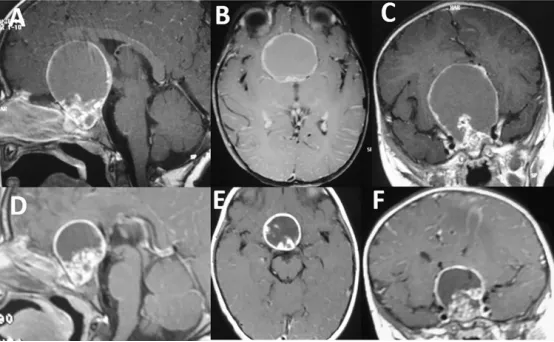

5岁女性患儿的颅咽管瘤(AC)T1加权MRI表现:矢状位(A)、轴位(B)和冠状位(C)序列均显示鞍区存在较小的实性肿瘤成分;同时可见巨大的鞍上/第三脑室囊性病变,其范围显著超过实性部分。

治疗随访结果(图D-F):经过3个周期腔内治疗(IA)后,2年复查MRI显示疾病控制良好,囊肿体积明显缩小;囊壁仍保持较厚形态,呈现"僵硬"外观,提示可能存在纤维化改变。